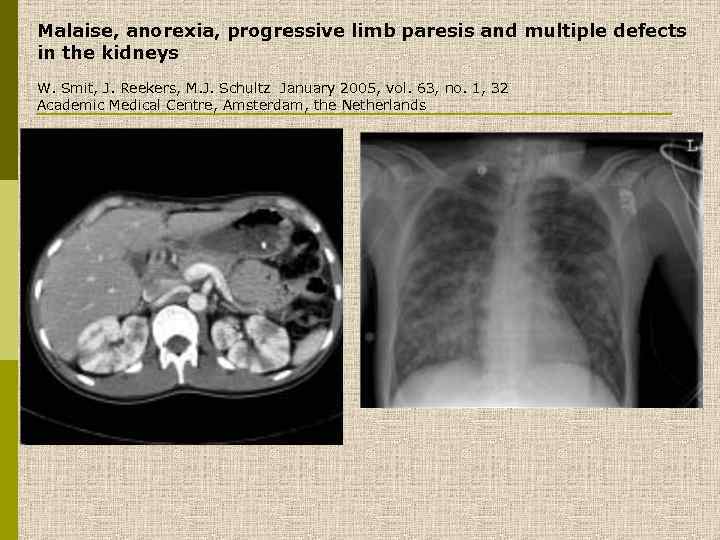

Malaise, anorexia, progressive limb paresis and multiple defects in the kidneys W. Smit, J. Reekers, M. J. Schultz January 2005, vol. 63, no. 1, 32 Academic Medical Centre, Amsterdam, the Netherlands